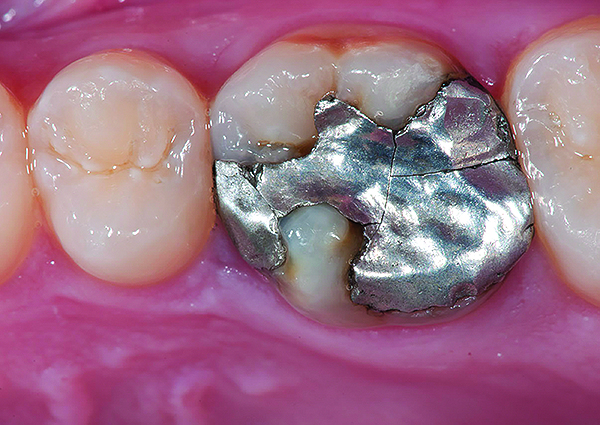

Fig 9. Preoperative view (Fig 9), preparation with composite block-out restoration (Fig 10), and final cementation of CL-IIb material (Fig 11) (final ceramic contour and stain by Steve Lee, CDT, MDC).

Figure 9

Fig 10. Preoperative view (Fig 9), preparation with composite block-out restoration (Fig 10), and final cementation of CL-IIb material (Fig 11) (final ceramic contour and stain by Steve Lee, CDT, MDC).

Figure 10

Fig 11. Preoperative view (Fig 9), preparation with composite block-out restoration (Fig 10), and final cementation of CL-IIb material (Fig 11) (final ceramic contour and stain by Steve Lee, CDT, MDC).

Figure 11

An example of this material subcategory is lithium disilicate (eg, IPS e.max®, Ivoclar Vivadent), a glass ceramic material composed of silica, lithium dioxide, alumina, potassium oxide, and phosphorous pentoxide. After the crystalline component has reached optimal growth through the manufacturing process, it is pulverized into powder and processed through a variety of different techniques.23 Lithium disilicate is indicated for the same clinical situations as other glass ceramics; however, when fabricated to a full-contour monolithic restoration and seated with resin cement, it is also appropriate for higher stress situations, such as those requiring full crowns, even on molars (Figure 9 through Figure 11).